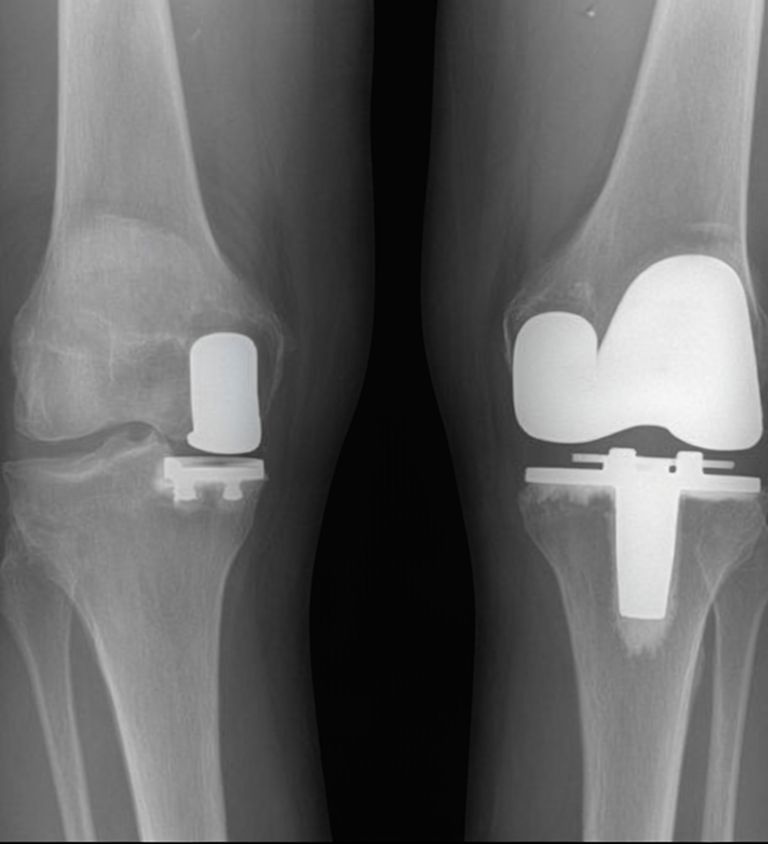

Partial Knee Replacement Surgery

A partial knee replacement, also known as unicompartmental knee replacement, is a surgical procedure to replace only the damaged portion of the knee joint, preserving the healthy parts.

Total Knee Replacement Surgery

A total knee replacement, or total knee arthroplasty, is a surgical procedure in which a damaged knee joint is replaced with artificial components to restore function and reduce pain.